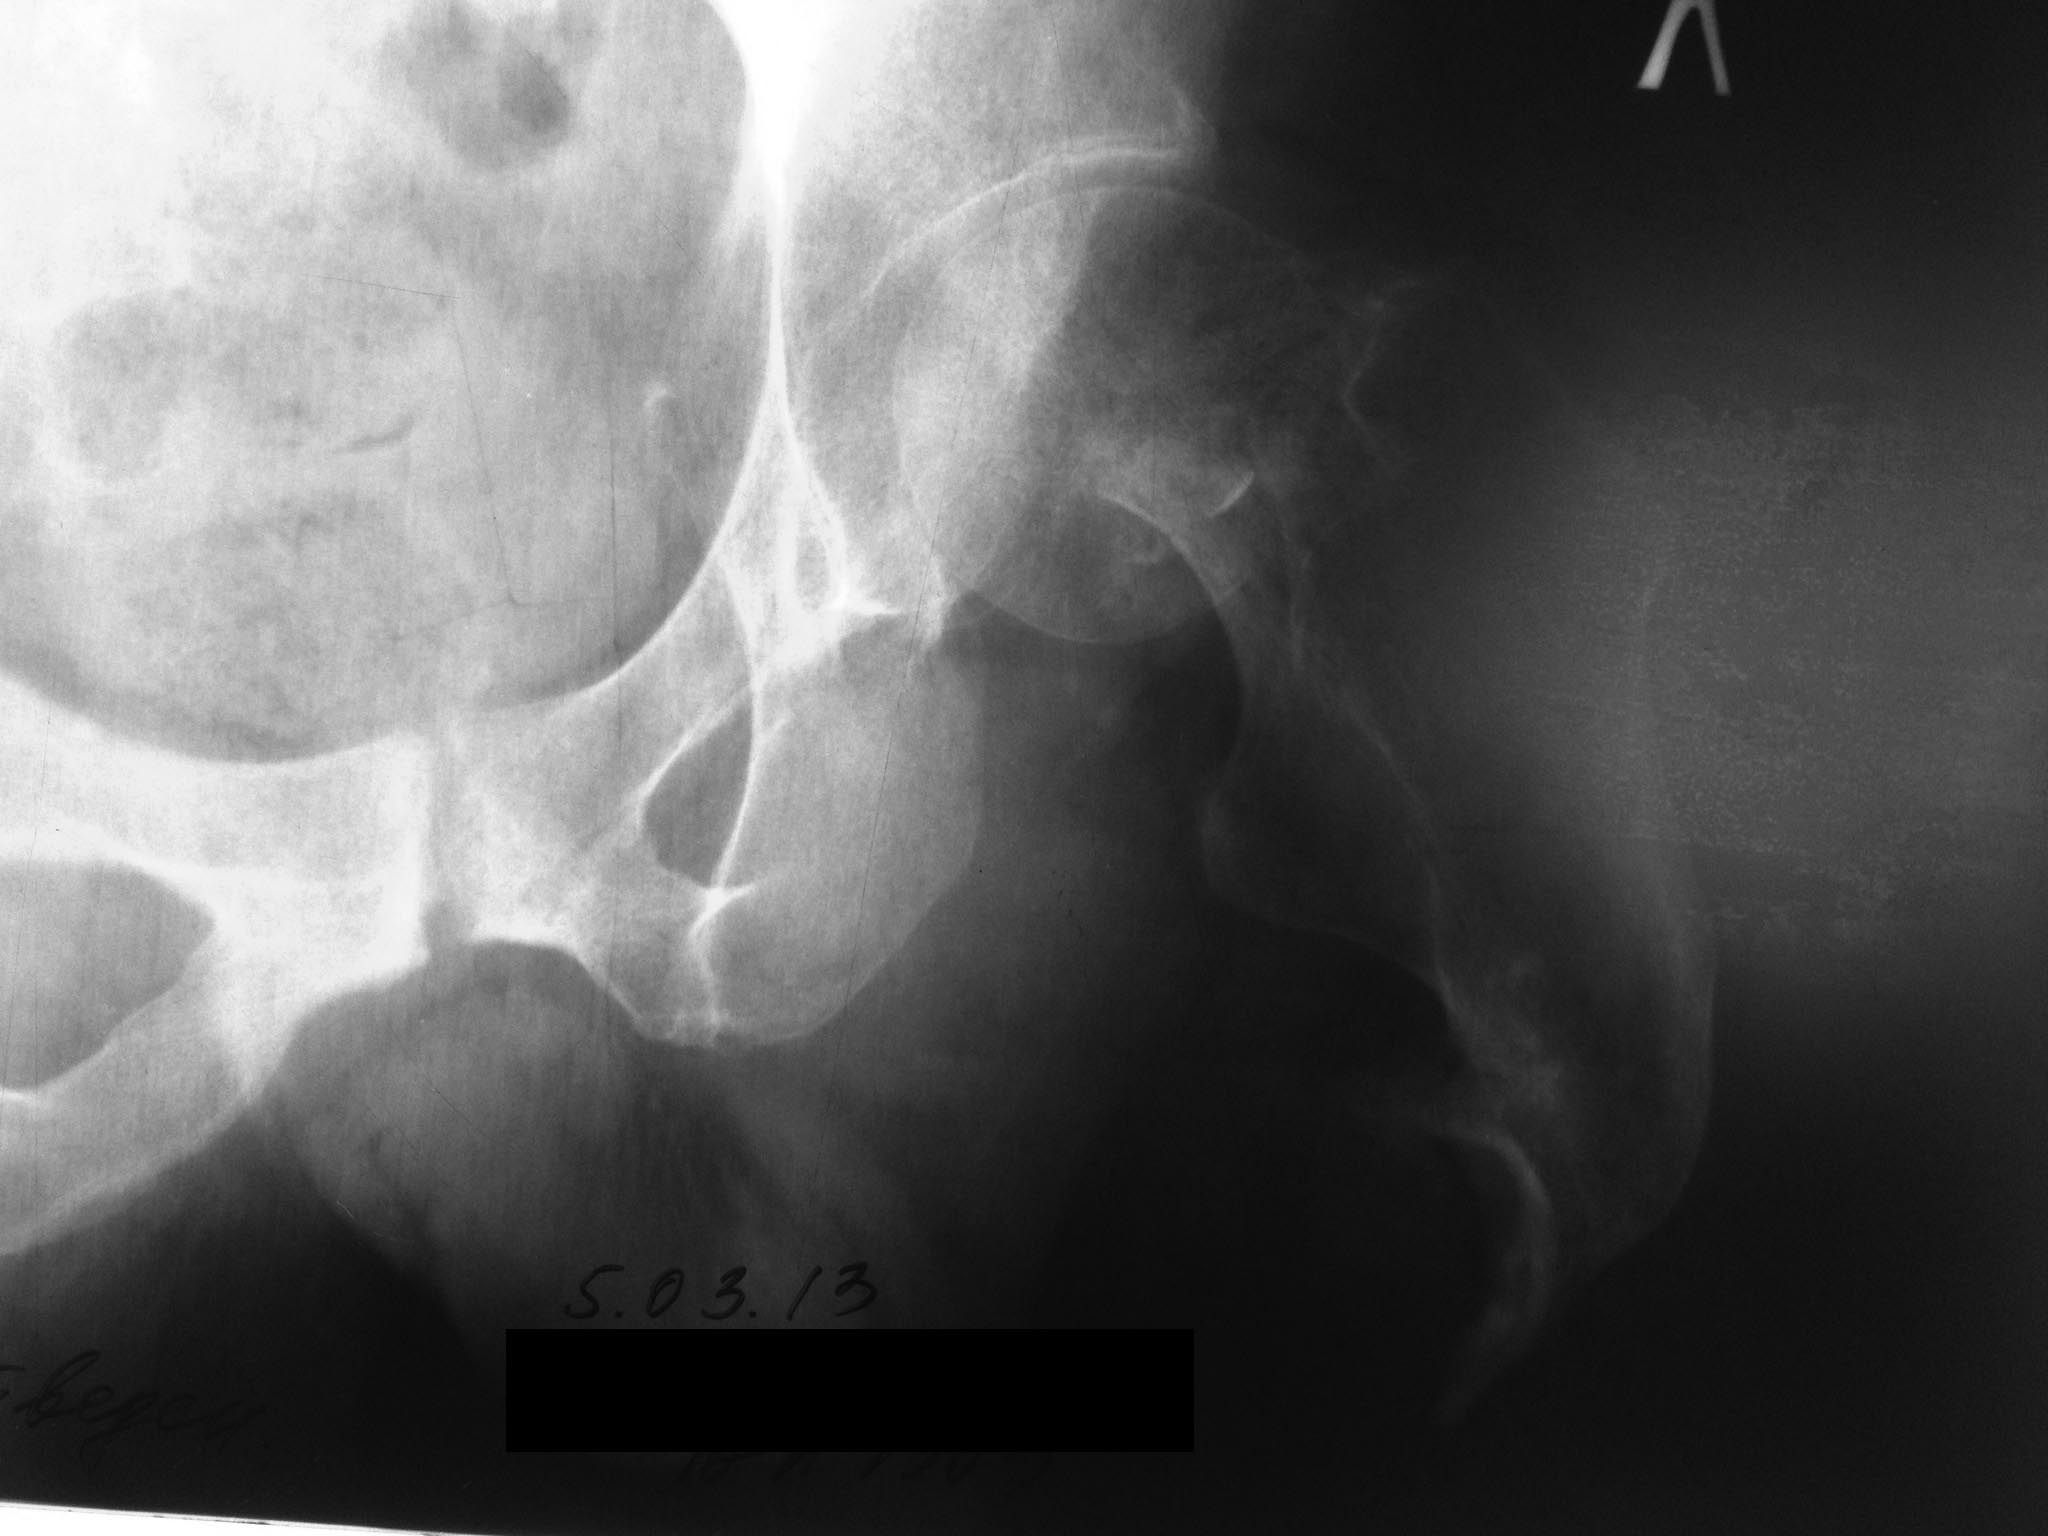

Здравствуйте, коллеги! Пациент 54 лет в середине 80х ампутация бедра во время боевых действий. В течении 30и лет использование экзопротеза, работал водителем. Шесть месяцев назад перелом шейки бедра.

В настоящее время внешний протез не опорен из за боли. Возможно ли поставить эндопротез? Какую лучше ножку? Стандартные короткие ножки ( Nanos) отпадают из- за пороза и короткой культи шейки. Может укоротить во время операции по длине культи ножку типа Corail?Насколько выше риск вывиха из- за непредсказуемого мышечного баланса?

Снимки наверное лучше предоставить посвежее. Учитывая возраст можно надеяться на консолидацию при остеосинтезе.